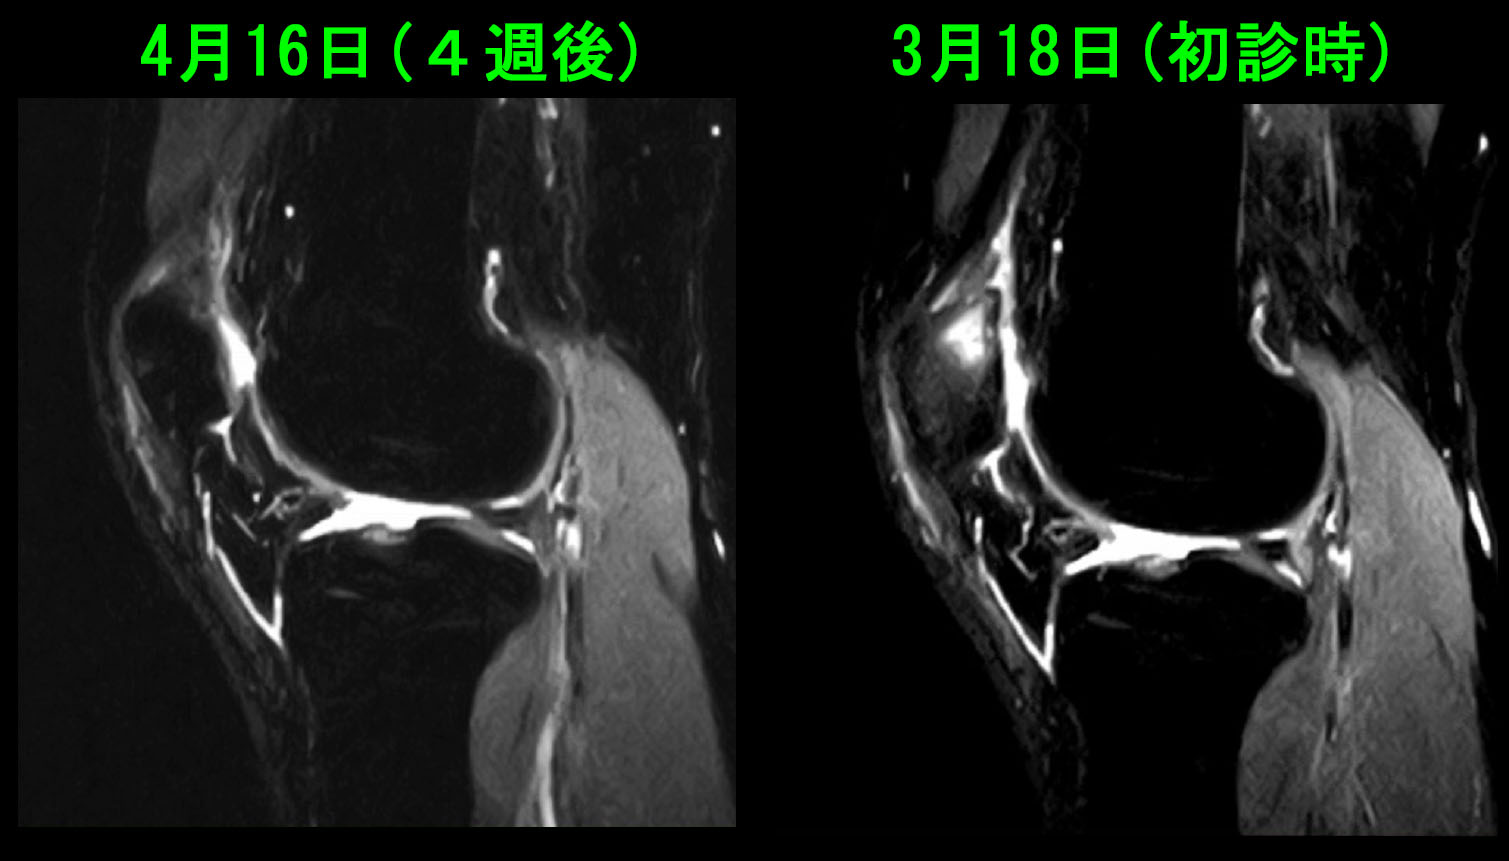

42才男 半年続く右膝痛・4週後MR.jpg

4週間後のMRI検査では膝蓋骨内の高輝度(白い状態)は軽減し、通常の骨に近づいています。痛みも軽減しています。

この患者さんで注目すべき点は骨の損傷を起こした場合、その修復が図れるまでは(正確な診断を受けて)安静を意識しなければ、痛みは軽減していかないということです。